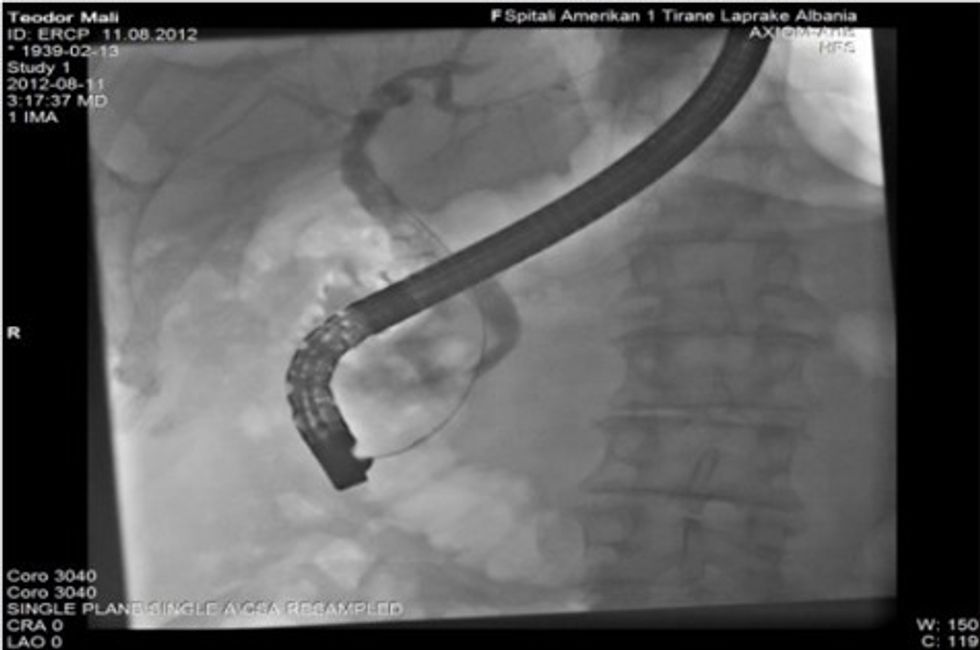

▪ Injektimi i kontrastit, fillimisht (në përdorim solucionin Omnipaque) në kanalin biliar dhe pankreatik. Filmimet me Xrreze menjëherë pas kontraktimit të këtyre kanaleve tregojnë për gjendjen në këto kanale, patologjitë prezente siç janë p.sh gurët në koledok, strukturat malinje etj. Çdo imazh filmik në Radioskopi ka karakteristika të veçanta në varësi të patologjive prezente. Në bazë të ndryshimeve në imazh radiografik ne mund të konstatojmë saktë për natyrën e sëmundjeve.

Pamja imazherike në Radioskopinë gjatë ERCP